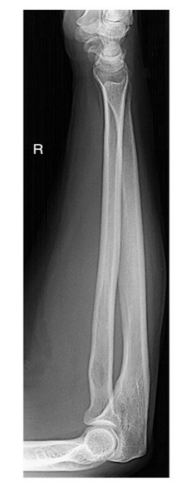

Evaluation criteria

Anatomy demonstrated: Elbow and wrist joints both included

Position: No rotation at wrist and elbow joints

Exposure: Optimal exposure factors

Image markers: “R” marker visible

Long bones are required how many projections?

Two

AP

Lateral